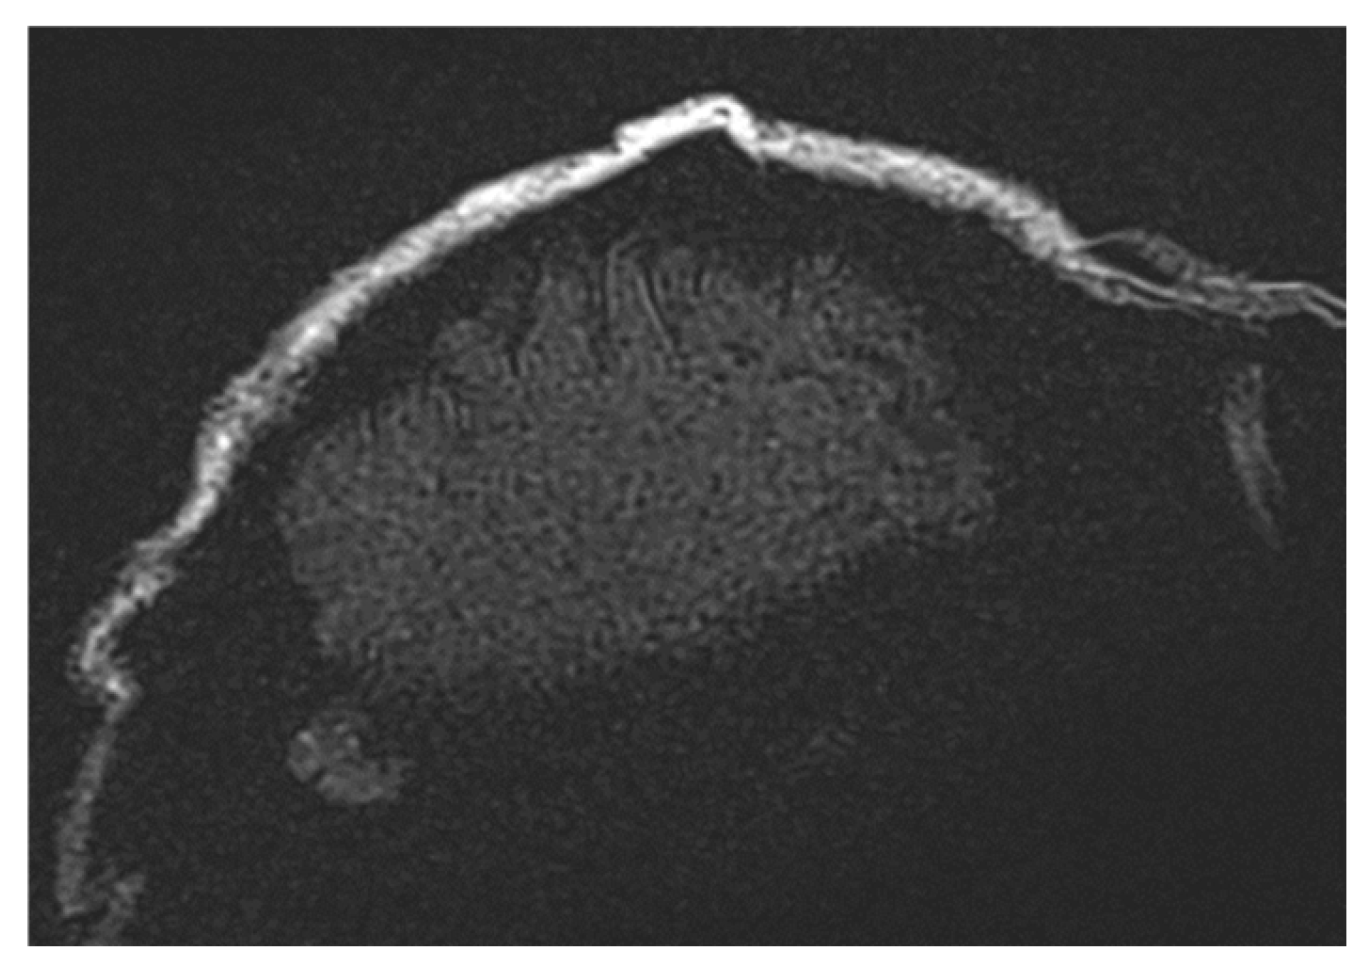

The Turbo Spin Echo (TSE) sequence was extensively utilized in this study due to its reduced sensitivity to susceptibility artifacts. This sequence is applicable to multiple contrast types (T1, T2, and Proton Density (PD)) and features an Echo Train Length (ETL) parameter, which controls sequence acceleration. Higher ETL values improve local image homogeneity but can also degrade spatial resolution. At extremely high ETL values (e.g., ETL = 45), a noticeable reduction in image quality is observed, as seen in Figure 6 (t2_tse_fs_tra sequence). Longer ETL values (tens of echoes) result in a blurred spatial resolution, which affects the quality of T2-weighted images.

Figure 6.

Images demonstrating the impact of varying Echo Train Length (ETL) values in the TSE sequence. Higher ETL values improve local image homogeneity but lead to a reduction in spatial resolution, with extreme ETL values (e.g., ETL = 45) causing noticeable image blurring, as observed in the t2_tse_fs_tra sequence.